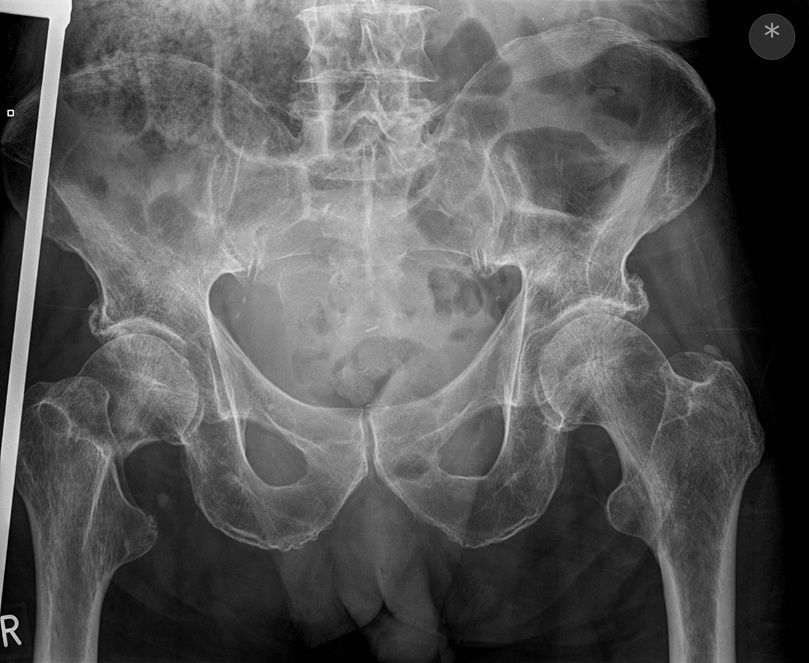

Question 4

Question

Which operation would you perform?

Answer

• THR

• Hemiarthroplasty